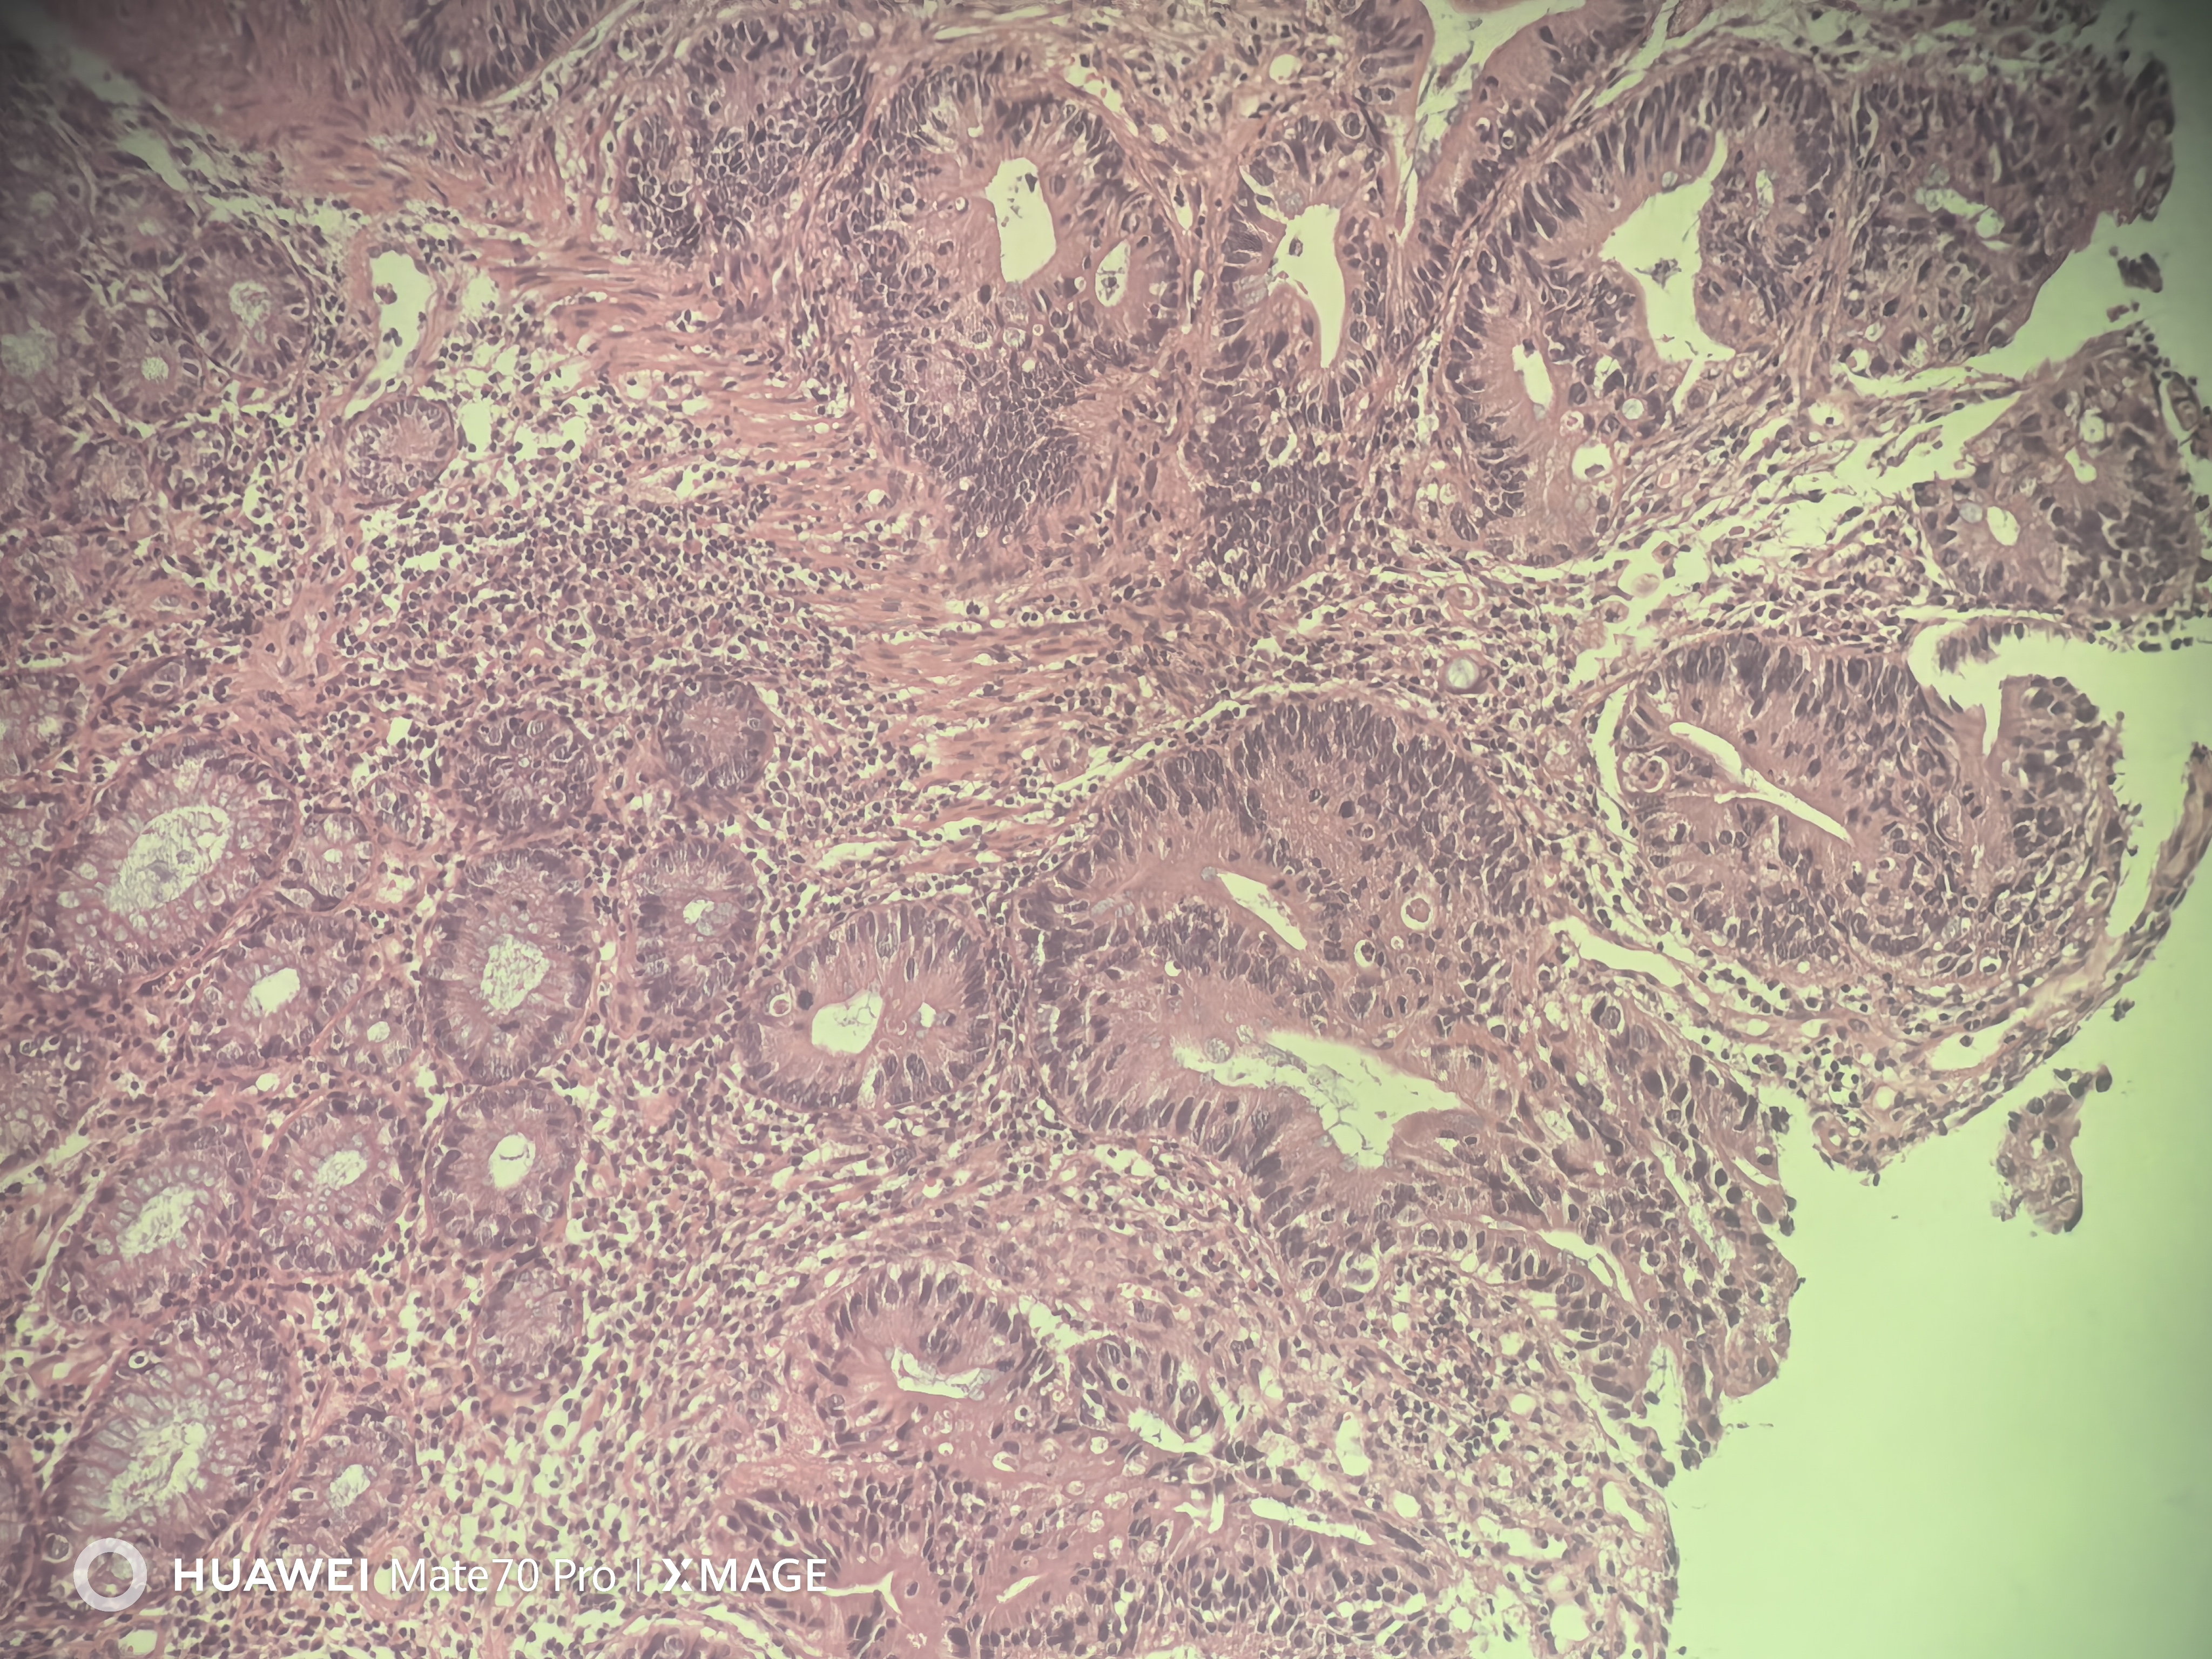

急!请老师帮忙看看

性别

男

年龄

78岁

临床诊断

结肠CA

一般病史

横结肠近肝曲不规则增生性肿物,环周生长,管腔狭窄,无法继续进境,表面充血糜烂坏死,质脆,易出血

标本名称

肠镜活检

大体所见

送检组织0.15x0.1x0.1厘米~0.2x0.1x0.1厘米

结肠腺癌

图1

腺癌

(横结肠肿物活检)腺癌。